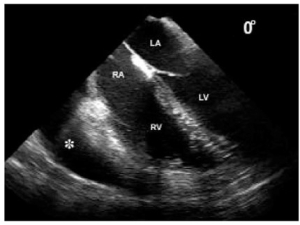

En prévention, la ponction trans-septal est ETO-Guidée. Il convient de vérifier la position dans l’OG suite à la ponction trans-septale, avant d’avancer le cathéter du dispositif. Cette vérification peut être faite par un contrôle visuel en ETO, ou lors de l’aspiration d’un sang artériel, ou par le monitoring hémodynamique continu (aspect d’une pression type OG) , ou par contrôle scopique avec une injection de produit de contraste.